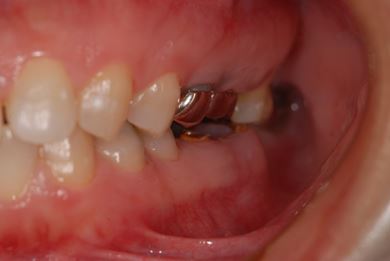

抜歯即日スピードインプラント治療+セラミック治療+歯肉歯槽骨整形術

| 治療方針 | 左下欠損部と保存不能の歯を抜歯し、インプラント治療にて機能的・審美的回復を行う。 | ||||||||||||||||||||||||||||||||

| 治療内容 | インプラント2本(抜歯即日スピードインプラント)、ハイブリッドセラミッククラウン2本、歯肉歯槽骨整形術 | ||||||||||||||||||||||||||||||||

| 総治療費 | 488,250円 | ||||||||||||||||||||||||||||||||

| 治療期間 | 1年4ヶ月 |